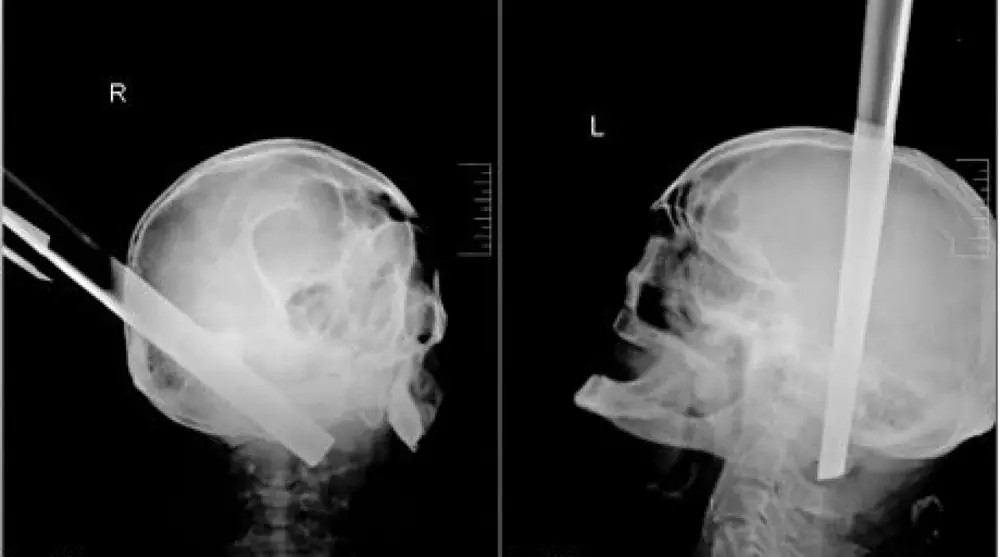

В России врачи спасли жизнь мужчине, который прибыл в больницу с металлической ножкой от табурета в голове, сообщает NEWSru.com Как поясняет издание, ножка пробила пациенту полость черепа в затылочной части и прошла на 11 сантиметров вглубь его основания сквозь вещество головного мозга. В экстренном порядке мужчине была проведена операция. По словам медиков, процедура прошла без осложнений, даже несмотря на удаление столь массивного предмета - у больного даже не возникло ожидаемого кровотечения. После операции, которая длилась около трех часов, мужчина две недели провел в нейрореанимации в тяжелом состоянии. Затем его состояние стабилизировалось. В настоящее время угрозы для его жизни нет. Он находится в сознании, может самостоятельно принимать пищу. "Он в сознании, имя и фамилию называет, но пока не помнит подробности, при которых получил травму", - сказал нейрохирург Павел Руденко.